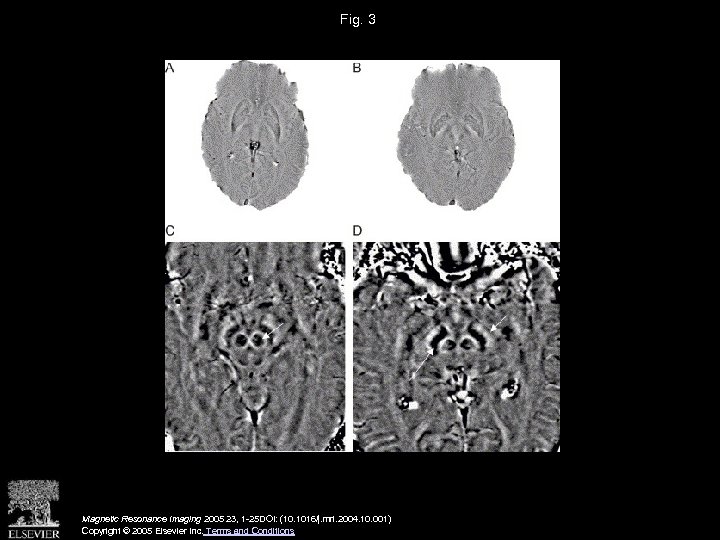

Fig. 3 Magnetic Resonance Imaging 2005 23, 1 -25 DOI: (10. 1016/j. mri. 2004. 10. 001) Copyright © 2005 Elsevier Inc. Terms and Conditions